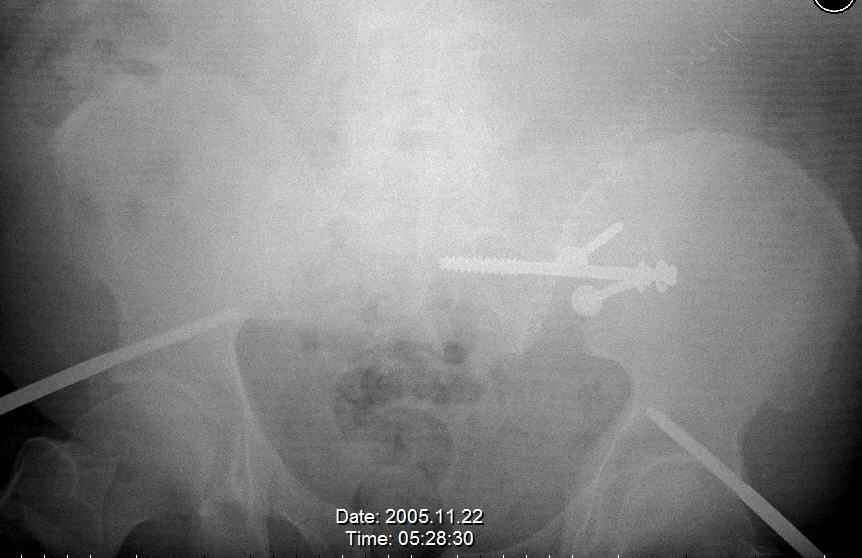

Hello gentlemen- Case is 52 YO male, fell out of treestand while deerhunting. He is 6 ft, approx. 260-275 lbs. Was hemodynamic unstable at local ER, sent to our Trauma center where circumferential pelvic binder placed and pt. stabilized with fluid, blood, and rewarming. Angiography not performed. An extraperitoneal bladder disruption was found, uro elected to treat non-operatively. Initial xray (not shown) demonstrated 5-7 cm wide at symphysis and SI joint. The first image attached is of CT once binder is in place. On post trauma day 5 the pt was taken to OR for ORIF of his iliac wing fracture and SI dislocation. The swelling/3rd spacing of fluid in the area of symphysis was profound, but quite acceptable posteriorly. Patient was prone for procedure, as I thought too difficult to fix the wing in lateral position. Of course the repair of wing was easy, but reduction of SI very demanding. The Floro images document the residual lack of reduction. That was the closest I could get it using 6mm joystick in wing, and clamp on sacrum and clamp through notch. The fixation was (initially) rigid. Anterior ex fix with supra-acetabular pins was placed due to condition of soft tissues, massive "beer-belly" overhanging the crest. Post trauma day ten patient's xray shows failure of posterior construct. Plan was to perform revision orif once soft tissues resolve considerably for full anrterior fixation and posterior fixation. However, while Im away for holiday (on Post trauma day 15), pt is developing septic clinical appearance, and trauma suspects pelvic abcess near symphysis and performs I and D - finds nothing but no primary closure performed. Posterior tissues/incision continue to look healthy. Now is post trauma day 17, pt is still tubed/on dopamine/and wbc still elevated, anterior incision still packed open. Clearly must get to bottom of possible sepsis, but then what? Thanks for you time - sorry for such lengthy clinical description. Thomas Schaller Kalamazoo, Michigan

5. Your caudal iliosacral screw is/was in his spinal canal... it's low and posterior and the lateral fluoro image confirms this... a postop CT will show it (or it's trail at this point)... canal screws do not hold.

6. Frames (even fancy new-style low ones) have poor mechanical stability when compared to symphyseal internal fixation...unstable rings in fat (and skinny) folks demand stable anterior and posterior stabilities... a frame

can't get you there... consider it a helper/support at best.